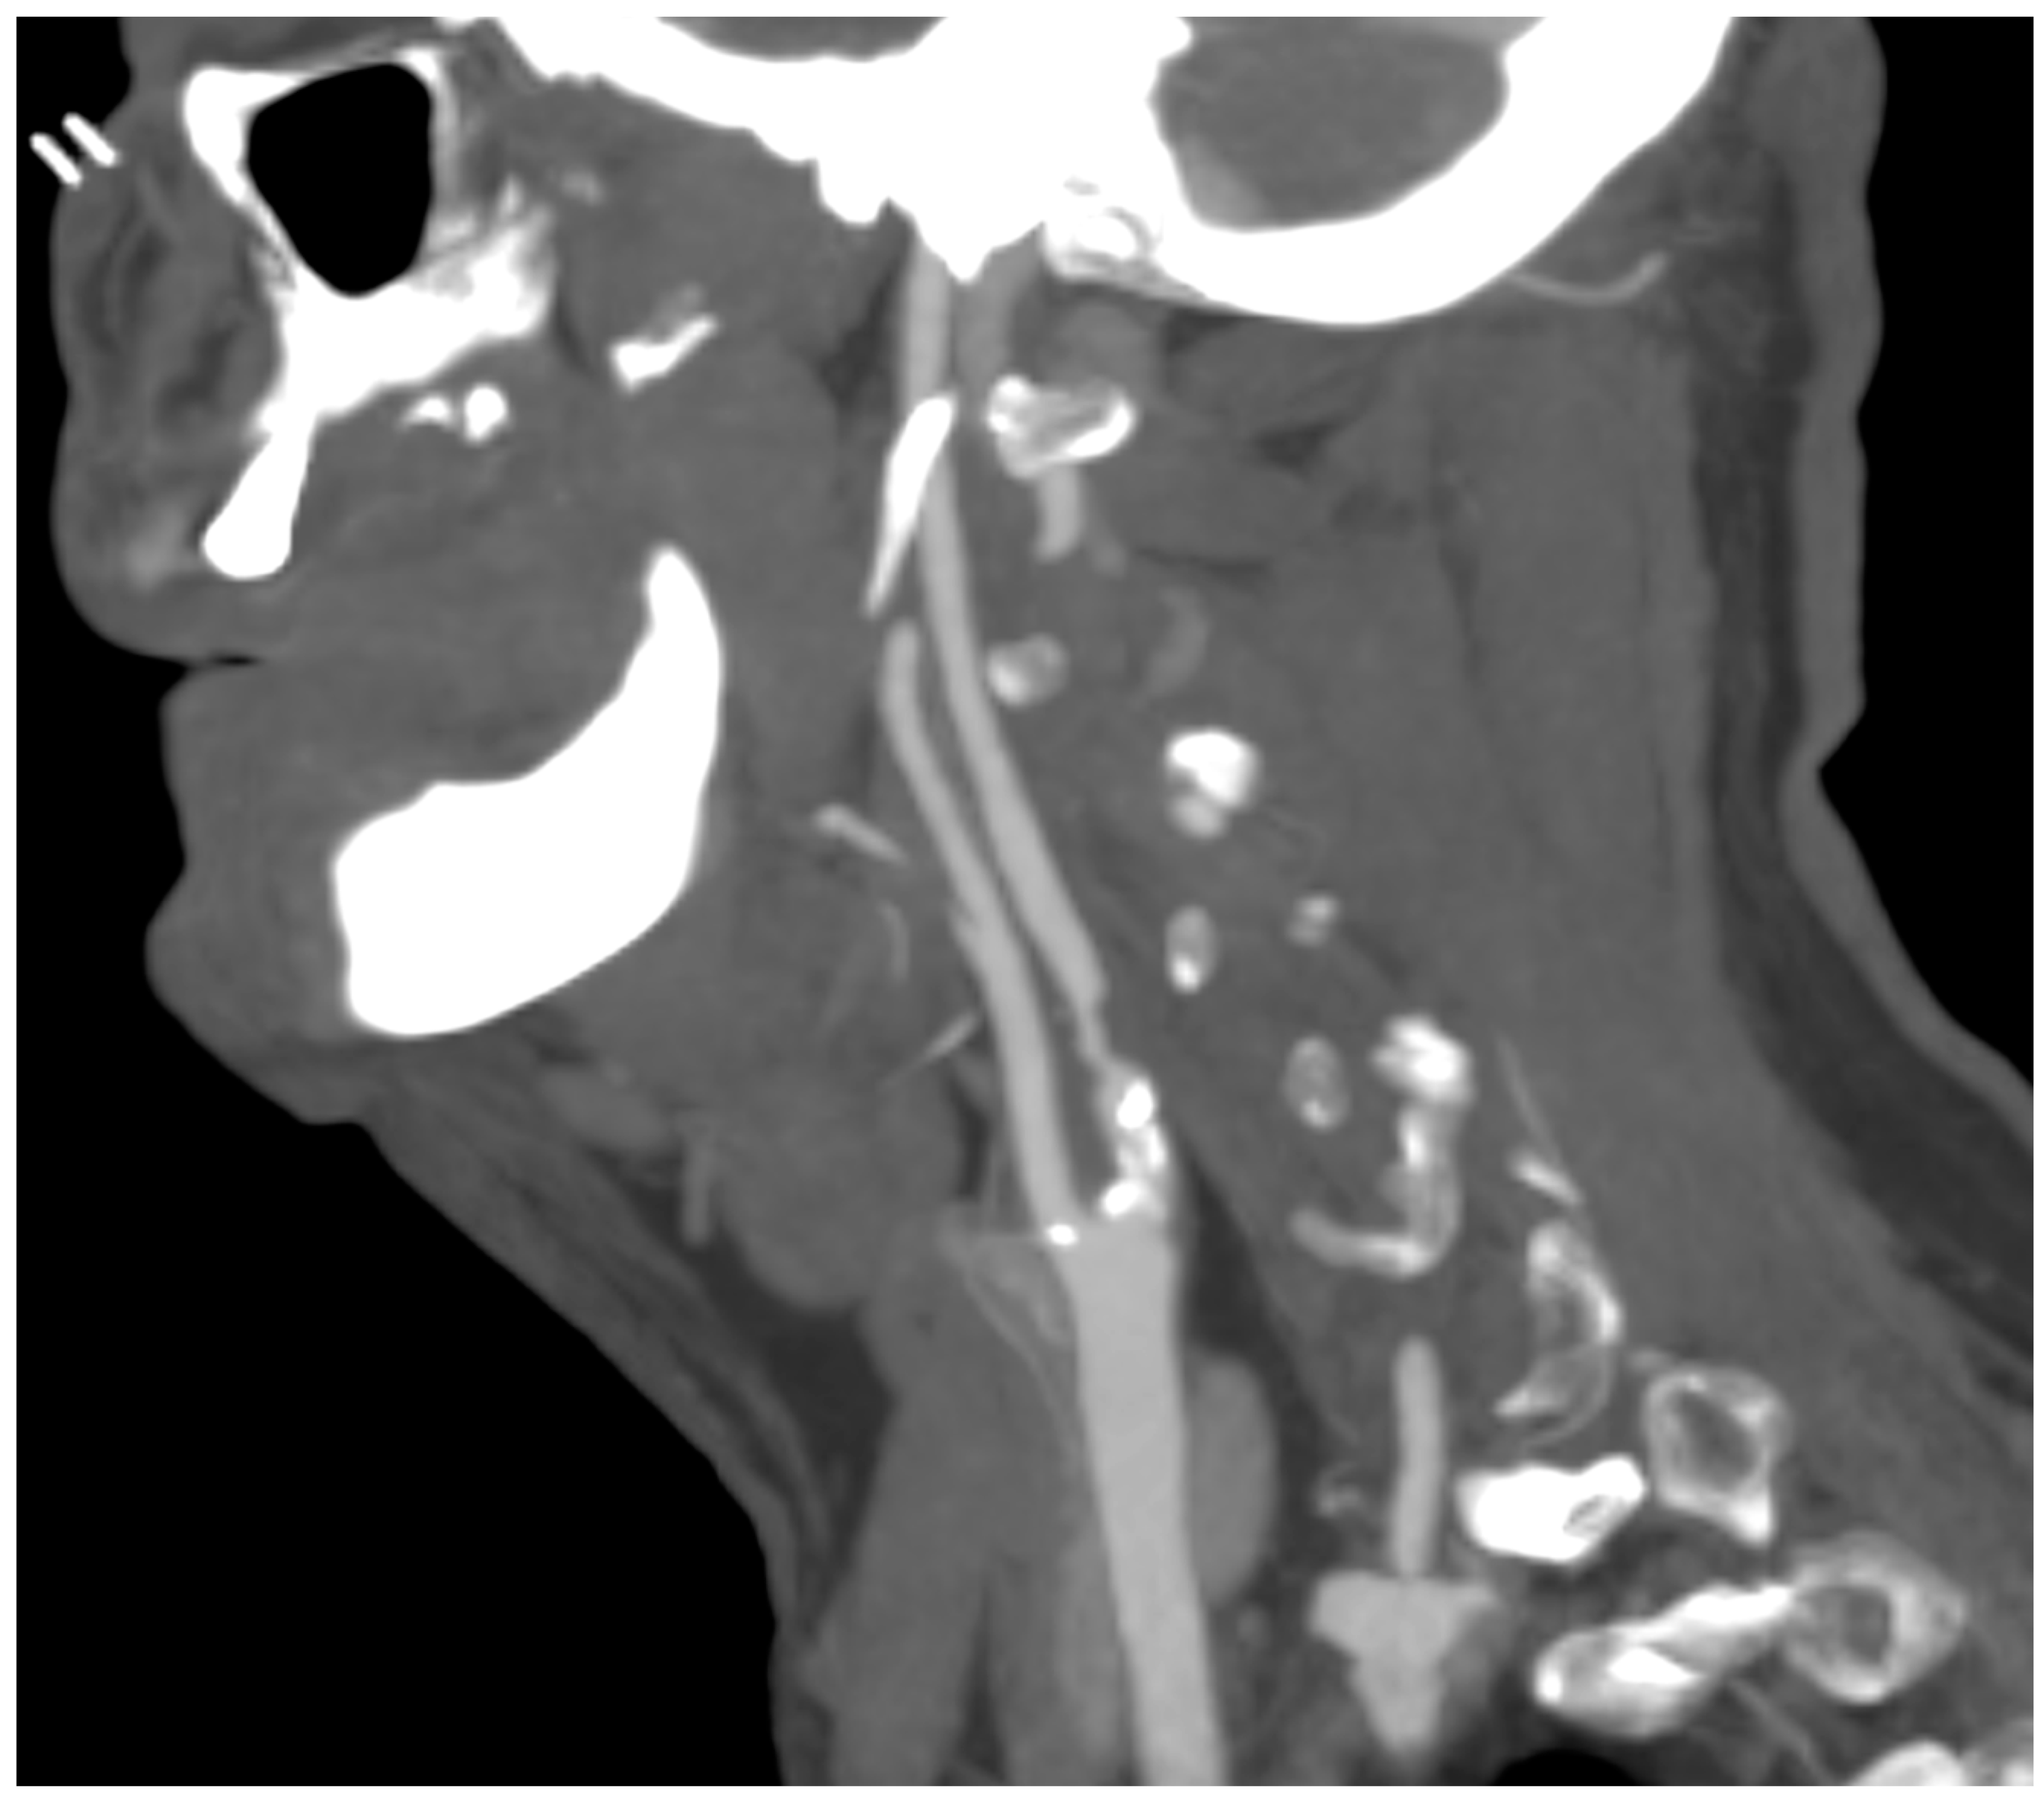

A computed tomography angiography (CT) was performed in patients presenting significative stenosis (>70%) according to DUS (Figure 3).

Figure 3.

CT angiography showing carotid plaque with significative stenosis.